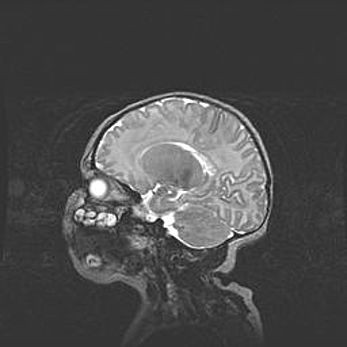

Мальформация Денди-Уокера. Киста задней черепной ямки.

Агенезия мозолистого тела.

Возраст: 2,5 месяца

Вес: 2420 г

Пол: женский

Окружность головы: 37 см

Срок гестации: 32 недели

Мальформация Денди—Уокера — редкий вид патологии ЦНС, представляющий собой врожденный порок развития каудального отдела ствола и червя мозжечка, ведущий к неполному раскрытию срединной (Мажанди) и латеральных (Лушка) апертур IV желудочка мозга. Для этогно синдрома характерна триада симптомов: гипотрофия червя мозжечка и/или полушарий мозжечка, кисты задней черепной ямки, гидроцефалия различной степени. В 70% случаев порок сочетается и с другими аномалиями головного мозга, в частности с агенезией мозолистого тела.